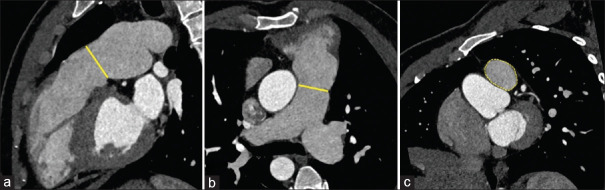

Transcatheter pulmonary valve implantation (TPVI) is the standard of care in patients with repaired tetralogy of Fallot (rTOF) presenting with right ventricular outflow tract (RVOT) dysfunction. However, the feasibility of TPVI is limited by the high cost and nonavailability of larger-sized valves for dilated native RVOT of rTOF patients. We report the first successful TPVI with a custom-made 35 mm balloon-expandable valve (Myval™) in a 30-year-old rTOF patient with severe pulmonary regurgitation and RV dysfunction.

Abstract Image